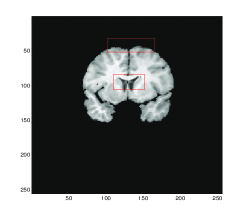

Figure 4 shows the transformed template images for all four methods. We can see that Gaussian curvature gives the best result inside the red boxes in comparison with the diffeomorphic demon, the linear and mean curvature models as depicted in Figure 4 (d).

Refer to caption

(a) Model D

(b) Model LC

(c) Model MC

(d) Gaussian curvature

Figure 4: Test 2: A pair of Brain MR images. Comparison of Gaussian curvature with competing methods. The transformed template image using (a) Model D, (b) Model LC, (c) Model MC, and (d) Gaussian curvature. Notice the differences of these three images inside the red boxes. Considerably more accurate results are obtained, particularly within these significant regions, by employment of the Gaussian curvature model.